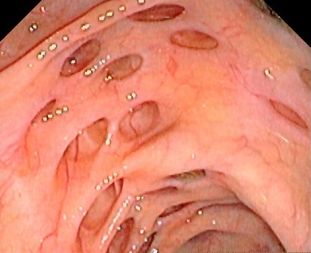

О дивертикулах и дивертикулите толстой кишки читайте специализированный сайт www.colorectalcancer.ru